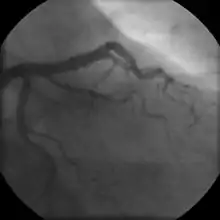

Coronary angiogram of a man

Coronary angiogram of a woman

For symptomatic people, stress echocardiography can be used to make a diagnosis for obstructive coronary artery disease.[68] The use of echocardiography, stress cardiac imaging, and/or advanced non-invasive imaging is not recommended on individuals who are exhibiting no symptoms and are otherwise at low risk for developing coronary disease.[68][69]

The diagnosis of microvascular angina (previously known as cardiac syndrome X – the rare coronary artery disease that is more common in women, as mentioned, is a diagnosis of exclusion. Therefore, usually, the same tests are used as in any person with the suspected of having coronary artery disease:[70]

Stable angina is the most common form of ischemic heart disease, and is associated with reduced quality of life and increased mortality. It is caused by epicardial coronary stenosis which results in reduced blood flow and oxygen supply to the myocardium.[72] Stable angina is characterized as short-term chest pain during physical exertion caused by an imbalance between myocardial oxygen supply and metabolic oxygen demand. Various forms of cardiac stress tests may be used to induce both symptoms and detect changes by way of electrocardiography (using an ECG), echocardiography (using ultrasound of the heart) or scintigraphy (using uptake of radionuclide by the heart muscle). If part of the heart seems to receive an insufficient blood supply, coronary angiography may be used to identify stenosis of the coronary arteries and suitability for angioplasty or bypass surgery.[73]